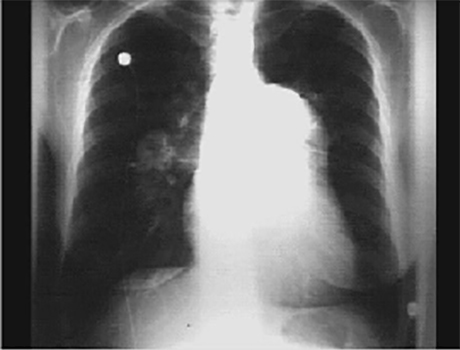

PA and Lateral

Click on the Xrays to enlarge them.

Choose the best interpretation of the chest X rays:

RV enlargement + ↓ pulmonary trunk + ↓ pulmonary vascularity

RV enlargement + ↑ central pulmonary

arteries + ↓ peripheral markings

RV enlargement + dilated pulmonary

trunk + ↑ pulmonary vascularity

RV enlargement +

left atrial enlargement

Bilateral pulmonary fibrosis +

mild cardiomegaly